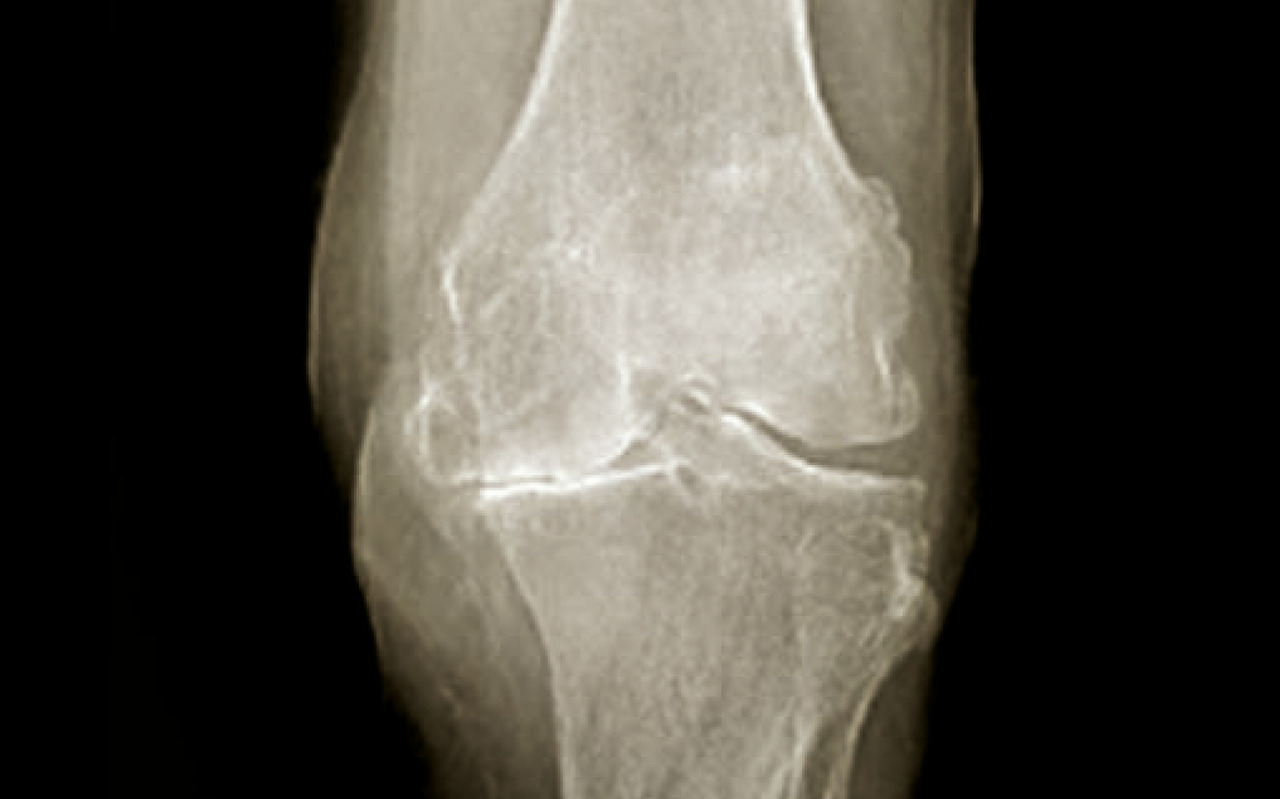

Là encore, de « simples » radiographies standard sont suffisantes et en aucun cas une IRM ou un scanner du genou ne doit être demandé en première intention. L’examen se fait de face et de profil, en appui bipodal, en rotation nulle, le genou en extension et avec un défilé fémoro-patellaire à 30° de flexion. Un examen en « schuss » (face, en charge, 30° de flexion) peut aussi être demandé. On y recherche un pincement fémoro-tibial interne ou externe, ainsi que des ostéophytes marginaux. On recherche sur le profil une ostéophytose située en avant et en arrière du tibia, ainsi que sur les condyles fémoraux. Il peut également exister une ostéocondensation sous-chondrale et des géodes dans les compartiments atteints (fig. 3 et 4).